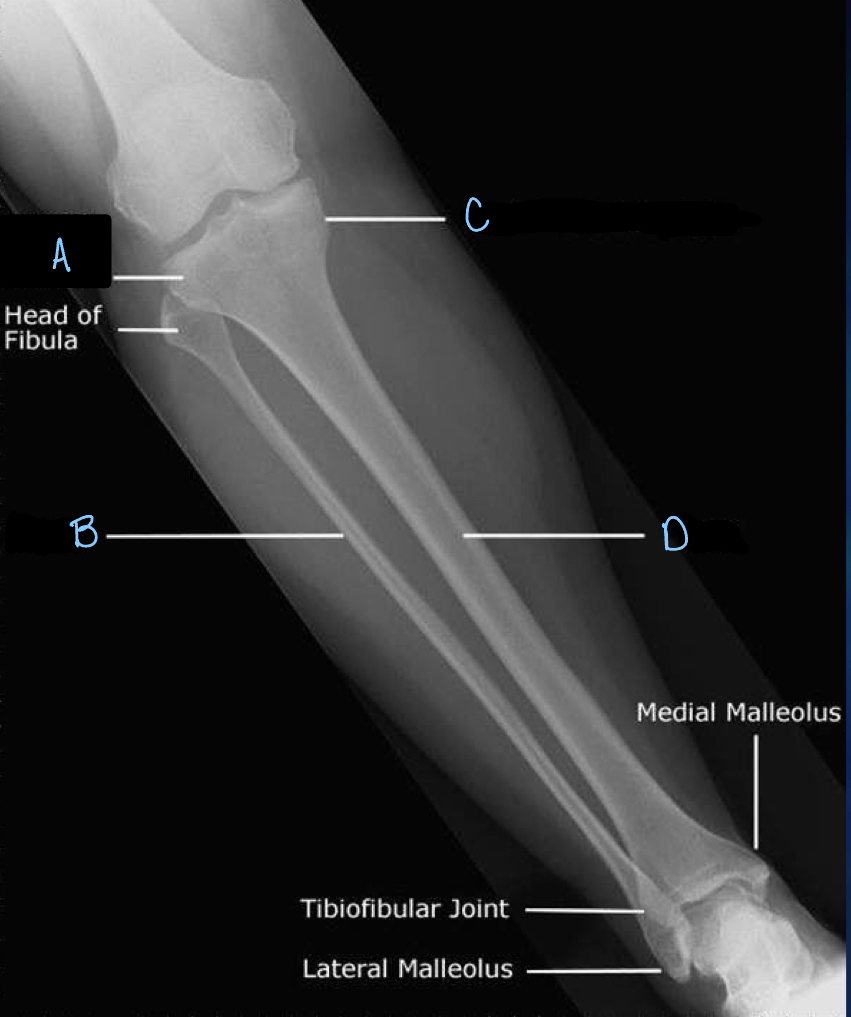

5

Q

What is A?

A

patella

6

What is B?

tibia

7

What is C?

fibula